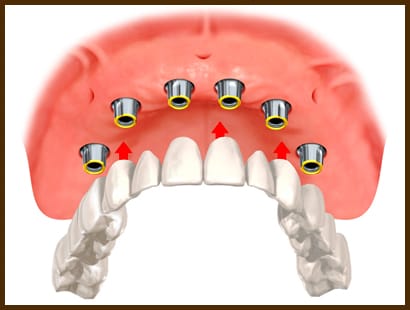

Chiar si atunci cand lipsesc toti dintii se poate apela la implante dentare pentru a creea lucrari fixe pe toata arcada dentara, un tratament cu adevarat spectaculos deoarece in aceste cazuri, foarte fecvent pacientul vine la clinica cu o proteza si pleaca cu o lucrare fixa.